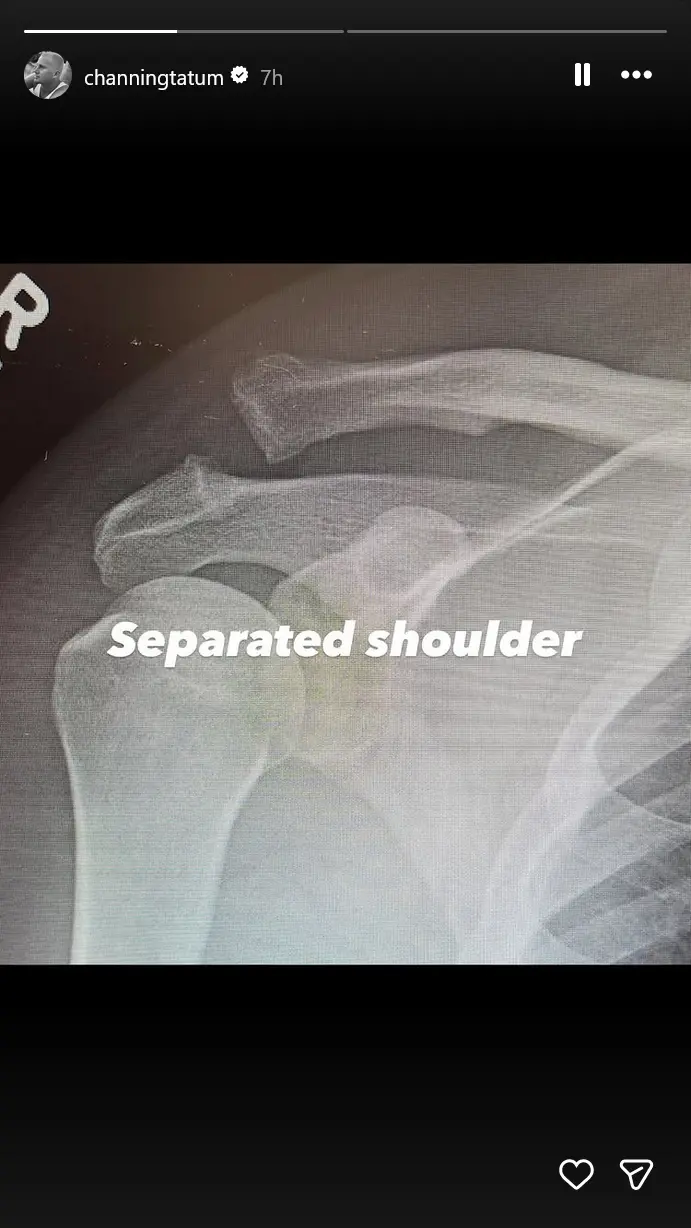

On his Instagram Story, he gave fans a closer look at the injury with “before and after” X-rays. The “after” image shows a surgical screw holding his shoulder in place. Tatum joked about it, captioning the photo, Screwed shoulder. Yay.